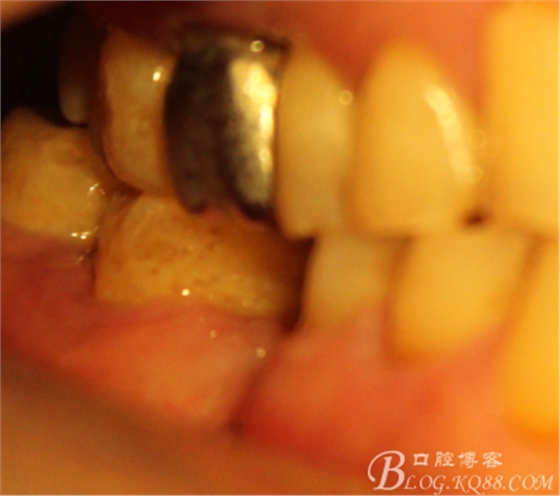

患者** 男性 年齡:65

主訴:右下牙齦反復(fù)流膿2月。

右下后牙2年前外院因咬物痛治療,后半年出現(xiàn)咬物不適,

牙齦腫脹2月,外院多次沖洗上藥未見(jiàn)好轉(zhuǎn),轉(zhuǎn)診要求檢查

頰側(cè)牙齦腫脹

因?yàn)樽笊献鲞^(guò)種植,口內(nèi)見(jiàn)

C6頰側(cè)骨缺損凹陷,對(duì)合金屬全冠,